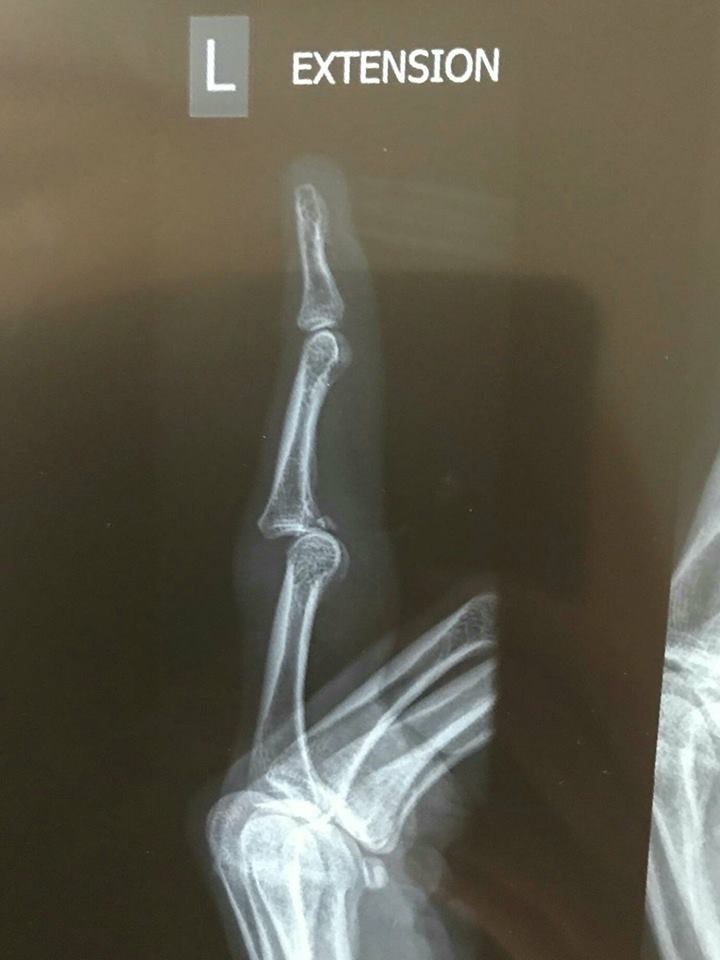

Scans, ultra sounds and X-rays revealed the extent of the damage but Hodges did not look at them, instead reading the injury summary.

Meeting with the specialist, Hodges finally looked at the actual scans to see what you now see, pictured.

"It was like: 'Holy $#!+' ... I couldn't believe it," she said.